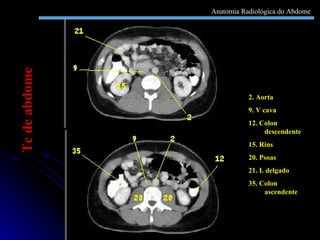

2. Aorta 9. V cava 12. Colon descendente 15. Rins 20. Psoas  21. I. delgado 35. Colon ascendente Tc de abdome Anatomia Radiológica do Abdome

2. Aorta 9.V cava 12. Colon descendente 15. Rins 20. Psoas 21. I. delgado 35. Colon ascendente Tc de abdome Anatomia Radiológica do Abdome